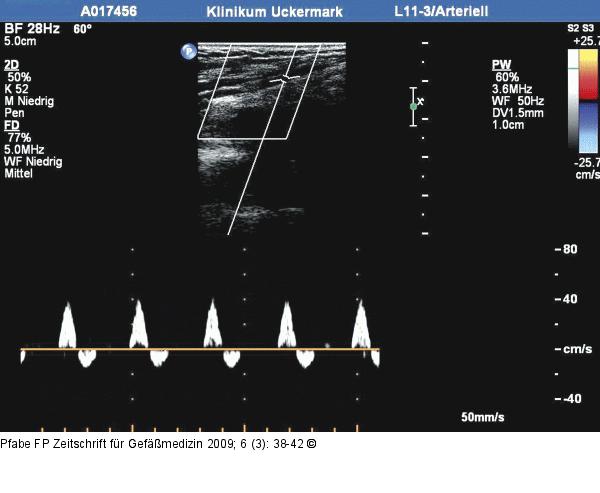

Abbildung 2: Arteria tibialis posterior

Unauffälliger Duplexbefund der A. tibialis posterior rechts. |